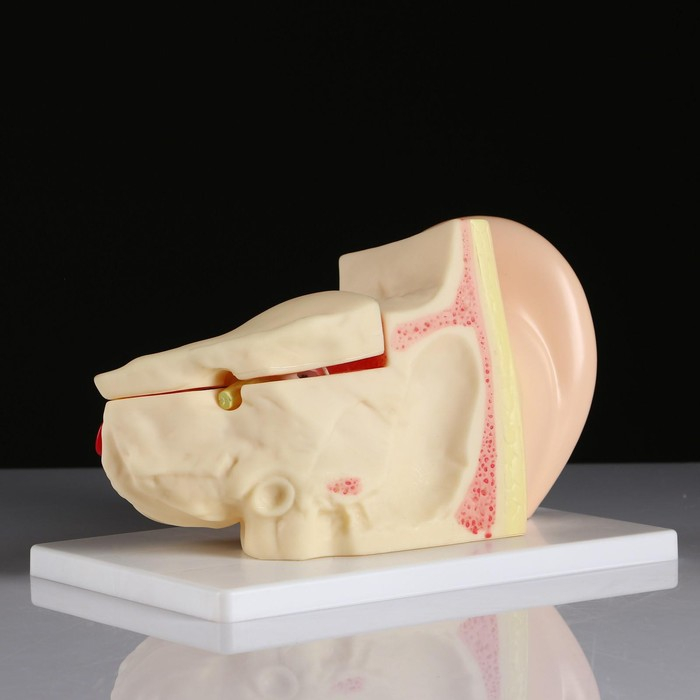

Анатомические модели